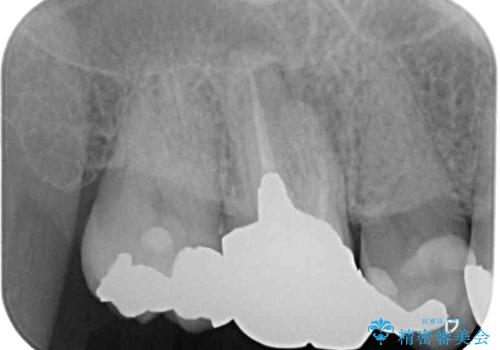

- 上の奥歯に咬んだときの痛みを感じて来院された患者様です。

まずは根管治療を行い、その後フルジルコニアクラウンにて補綴することとしました。

根管治療後には痛みが引き、半年後のレントゲンからは根尖部の病変が縮小している様子が分かりました。

咬んだときの感触も良好で、患者様には大変満足していただきました。